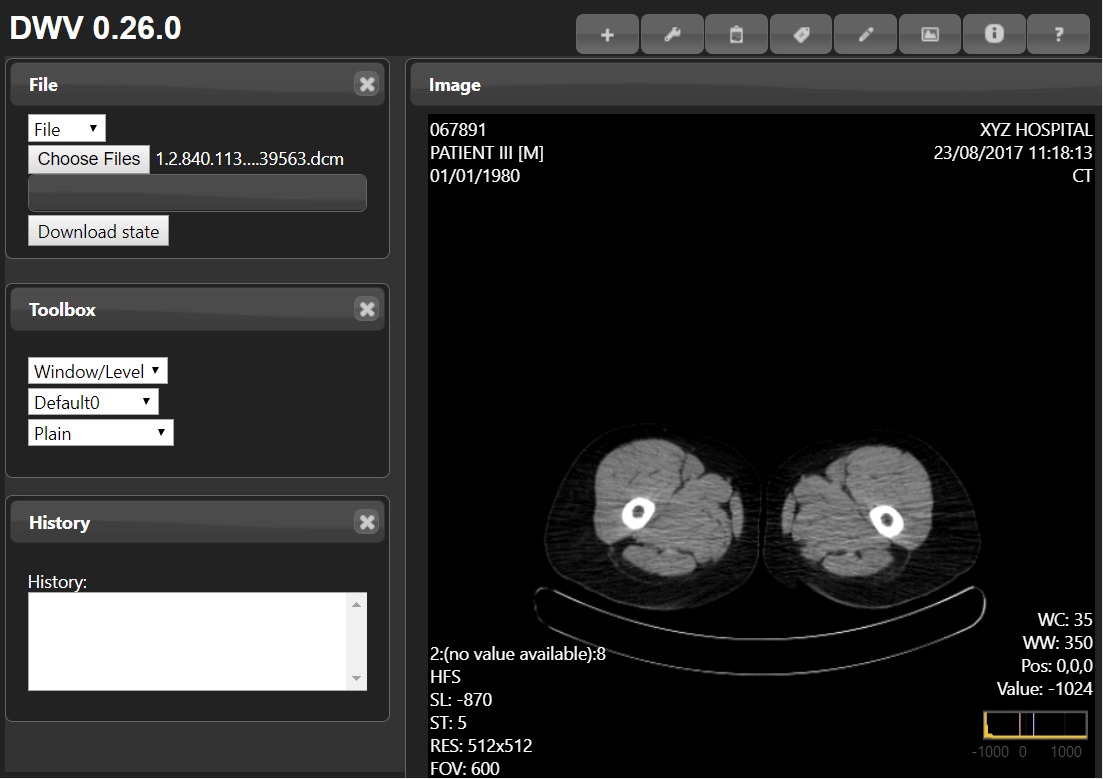

This is a browser-based DICOM viewer, which means it cannot be downloaded, but can be accessed through any device with an internet browser—your laptop, phone, tablet, or even smart televisions. Only basic manipulation of the image (drag, zoom, contrast) can be done, and as this is view-only, export is not possible. The application requires some technical skill to navigate around, but videos and support is offered.

| 8. | DICOM Web Viewer | Browser-based (JavaScript and HTML 5) | Not available (zero footprint) | N | N | N | N.A. | N.A. | N.A. | Free to use |